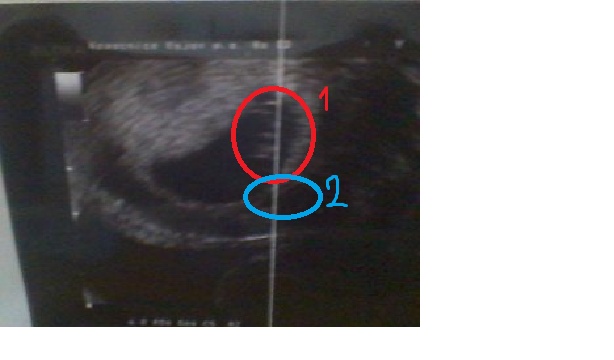

Tak jsem byla na utrazvuku, a bylo mi řečeno, že hemák je furt stejný :/ prckovi bije srdíčko ale je mini a furt mi říkají že jsem sedmý plus 4.... :/

1) plod 2)hematom